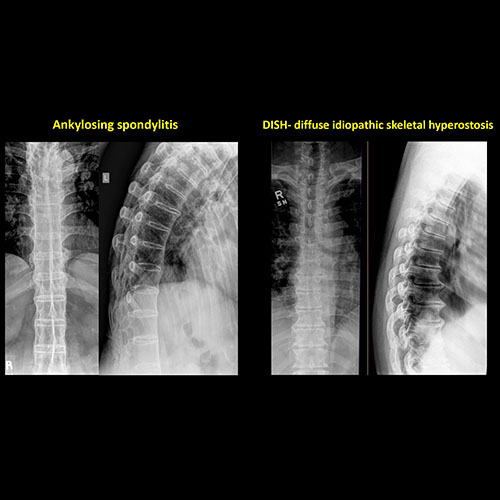

There is an oblique fracture with avulsion through the anterior inferior T9 vertebral body. The posterior elements are intact. There is excessive calcification of the anterior longitudinal ligament and there are continuous osteophytes in a pattern consistent with DISH (Diffuse Idiopathic Skeletal Hyperostosis).